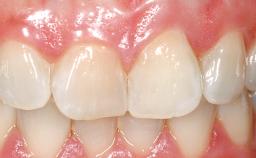

Immediate Flapless Placement of an Implant in a Maxillary Right Lateral Incisor Site

This 43-year-old male patient, a non-smoker, came to our practice because of a fracture of tooth 12 caused by a bicycle accident. Due to the combined para- and infrabony crown and root fracture, tooth extraction, and subsequent implant placement were suggested to the patient as the therapy of choice. The patient had high esthetic expectations with regard to the treatment outcome and asked for an immediate fixed provisional restoration. His individual esthetic risk profile summed up to a medium esthetic risk.

Loading Protocol Immediate

Provisional Implant-Supported Prosthesis Prosthodontic margin > 3 mm apical to mucosal margin Prosthodontic margin > 3 mm apical to mucosal margin